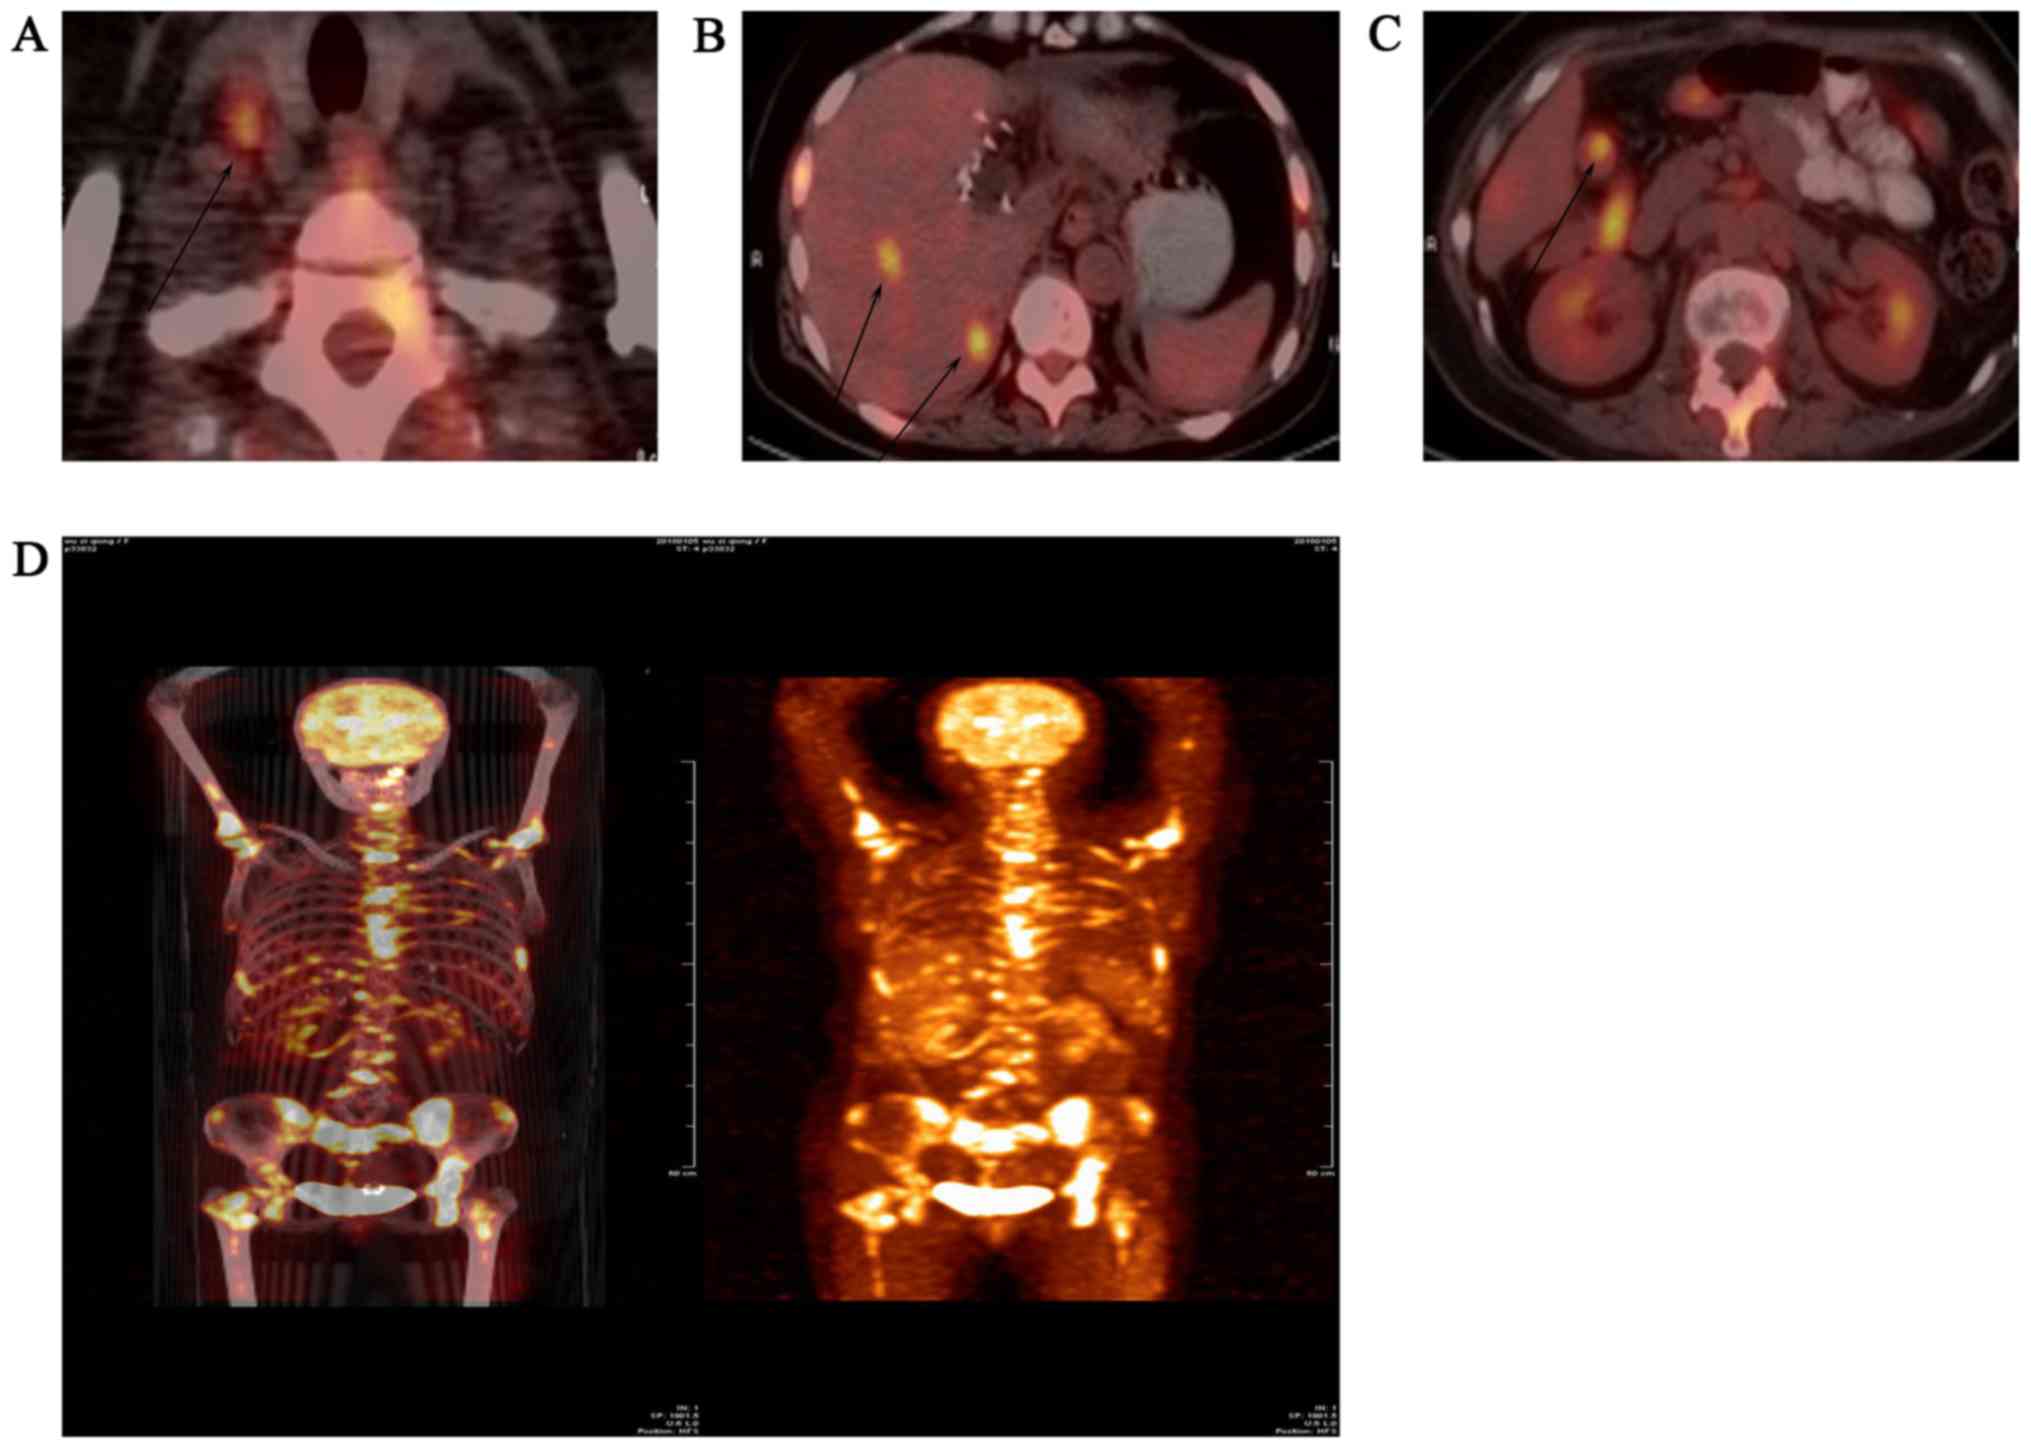

A 55-year-old woman presented with chest and back pain of unknown etiology. The patient was admitted to the West China Hospital (Chengdu, China) for further examination and treatment. Laboratory data revealed increased levels of α-fetoprotein (AFP), serum carbohydrate antigen (CA)125 and NSE, which were 23.41 ng/ml (normal range <20 ng/ml), 62.26 U/ml and 127.9 ng/ml, respectively. The AFP values associated with primary hepatocellular carcinoma are generally known to be >500 ng/ml for 4 weeks, or 200-500 ng/ml for 8 weeks. Therefore, the diagnosis of primary liver cancer in this patient was not considered likely. CA125 is widely present in mesothelial tissue and is currently the most important ovarian cancer-associated antigen. CA125 is the most reliable diagnostic indicator for ovarian cancer, and its normal level is <35 U/ml, whereas NSE is mainly used for the diagnosis of neuroendocrine tumors, with a serum reference value of <12.5 ng/ml. Contrast-enhanced computed tomography (CT) examination revealed low-density tumors sized 4.6 and 4.4 cm in the caudate and left internal lobe of the liver, respectively (Fig. 1A and B). There were multiple enlarged lymph nodes along the abdominal aorta, the hepatogastric and gastrosplenic ligaments, and in the space between the portal vein and the inferior vena cava (Fig. 1C). The patient was subjected to left three hepatic resection (including left inner lobe, left outer lobe and right anterior lobe resection), abdominal lymph node dissection, liver tumor radiofrequency ablation, hepatic caudate lobe resection, intestinal adhesion release, repair of vena cava damage, portal vein repair and hilar cholangioplasty in our hospital. The liver margin of the surgical specimen was not invaded by cancer. Subsequent immunohistochemical examination did not rule out the possibility of a gastrointestinal origin, and gastrointestinal endoscopy and positron emission tomography (PET)-CT were performed to exclude distant metastasis. Upper gastrointestinal endoscopy revealed chronic non-atrophic gastritis and esophagitis (grade B). Endoscopic examination of the lower digestive tract detected polyps of the colon, diagnosed as tubular adenomas following biopsy and histopathological examination. The PET examination demonstrated active glucose metabolism in the liver, cervical lymph nodes, abdominal lymph nodes and bones, mostly due to tumor metastases (Fig. 2). There was no evidence of intestinal, ovarian or other metastases.

Figure 1.

(A and B) Computed tomography of liver revealed two soft tissue masses of slightly lower density in the liver, sized ~4.6 and 4.4 cm, with enhancement of the margins (arrows). (C) Computed tomography of the abdomen revealed multiple lymph node enlargements along the abdominal aorta, hepatogastric and gastrosplenic ligaments and in the space between the portal vein and the inferior vena cava (arrow).